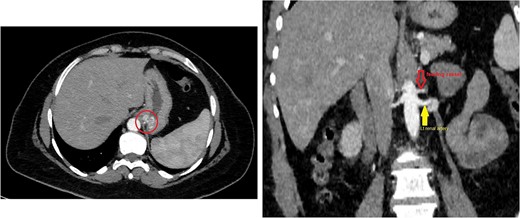

The CT scan confirmed a Dieulafoy’s lesion from the left phrenic artery (Fig. 2a and b) and showed collateral vascular channels around the pancreas with near-complete celiac trunk compression by the median arcuate ligament (Fig. 3). She underwent left phrenic artery embolization without complications, while asymptomatic celiac artery compression was treated conservatively. A follow-up endoscopy showed no bleeding or ulcers (Fig. 1d). Later, she developed severe left flank pain, and a contrast-CT revealed splenic vein thrombosis with infarction (Fig. 4), which was treated conservatively. Additionally, an incidental finding of left pleural effusion was drained. Rising inflammatory markers were managed with analgesics and IV antibiotics. She was discharged with outpatient follow-up, and at her 10-day visit, she reported improvement, stable hemoglobin, and normal inflammatory markers. She was satisfied, and a follow-up endoscopy was planned in 2 weeks.

(a) Axial CT angio of the abdomen shows a small area of enlarged tortuous blood vessels seen along the posterior cardia of the stomach; these findings are suggestive of Dieulafoy lesion. (b) Coronal abdominal CT images show the feeding blood vessel arising from the descending abdominal aorta located just superior to the origin of the left renal artery.